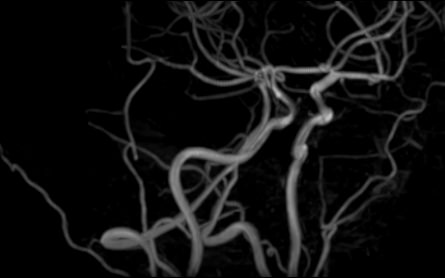

Стандартная МРТ головного мозга дает важную информацию о состоянии и структуре мозговой ткани для выявления большого числа заболеваний, в том числе опухолевых образований, демиелинизирующих заболеваний, воспалительных процессов головного мозга и мозговых оболочек. Стандартную МРТ головного мозга дополняет МР-ангиография, которая отображает состояние артериальной системы кровоснабжения головного мозга. МР-венография головного мозга позволяет детально изучить особенности анатомического и функциональной состояния венозного русла головного мозга.

Компьютерная программа обрабатывает данные, полученные при сканировании, и формирует объемные изображения как самого мозга, так и сосудистой системы в отдельности без прилегающих тканей. Обе методики применяются одновременно и взаимодополняют друг друга, давая полную диагностическую картину.

• патология со стороны сосудов головного мозга (аневризмы, сужение просвета сосудов, сосудистые мальформации).